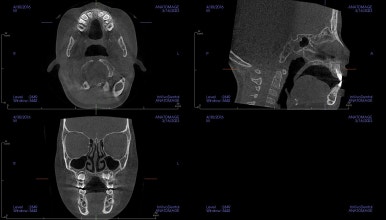

다양한 골격분석 뿐만 아니라 호흡기 구조까지 살펴보게 되는데요.

골격의 주걱턱 패턴이 심하지 않은데, 앞니가 반대교합인 경우는 반드시 호흡문제를 함께 봐야 됩니다.

원인을 알아야 치료 후에도 그 결과가 잘 유지될 수 있거든요.

이번 환자분도 호흡기 문제에 기인한 혀의 위치 불량으로 아래 앞니가 자꾸 밀려나는 상태였습니다.